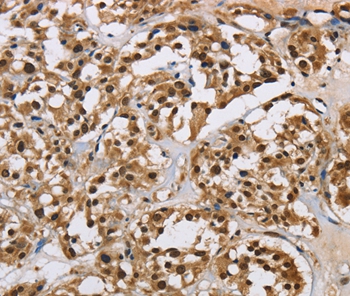

Immunohistochemical analysis of paraffin-embedded Human thyroid cancer tissue using #37624 at dilution 1/40.